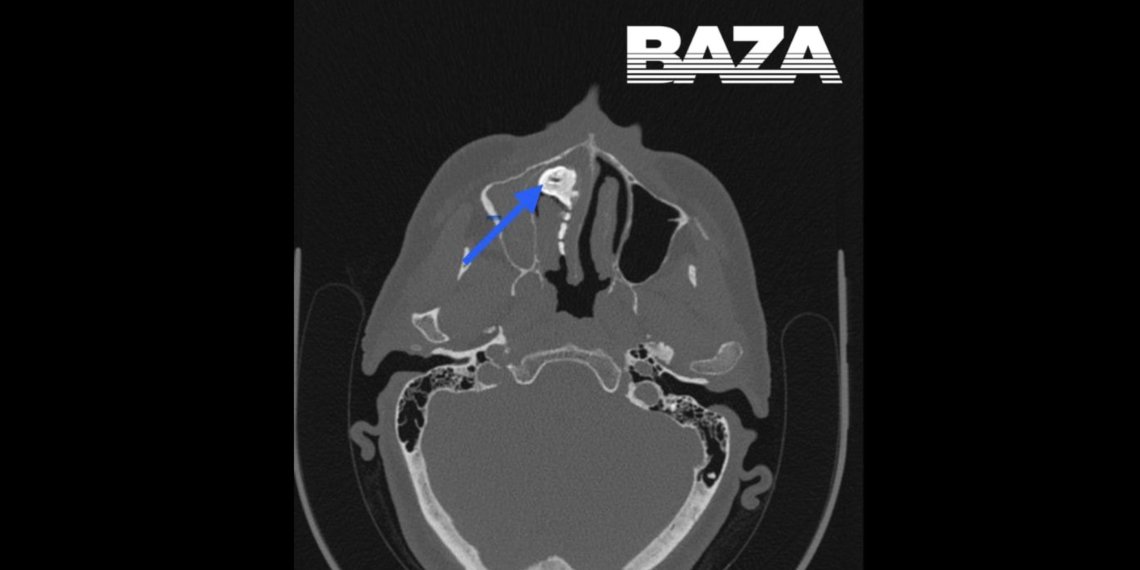

Женщина обратилась к врачам, потому что ей стало тяжело дышать, она чувствовала неприятный запах, боль в носу и странные выделения. Врачи сделали рентген и обнаружили в голове женщины крупный предмет. Объяснить, что это может быть, пациентка не смогла. Однако вспомнила, что несколько лет назад вдохнула что-то мелкое, но дискомфорта после этого не испытывала, поэтому за помощью не обратилась. Неприятные симптомы появились только несколько месяцев назад.

Женщине провели операцию под местной анестезией. Крупный предмет извлекали несколькими частями. Это оказался орех, покрытый слизью полости носа. После операции все симптомы сразу же прошли. Женщину уже выписали.